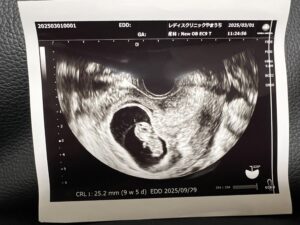

エコーを覗く先生の表情が、途中から少し曇ったのを今でも覚えています。

そして告げられた言葉は——「絨毛膜下血腫」。

- 超音波(エコー)で「黒い影」のように見える